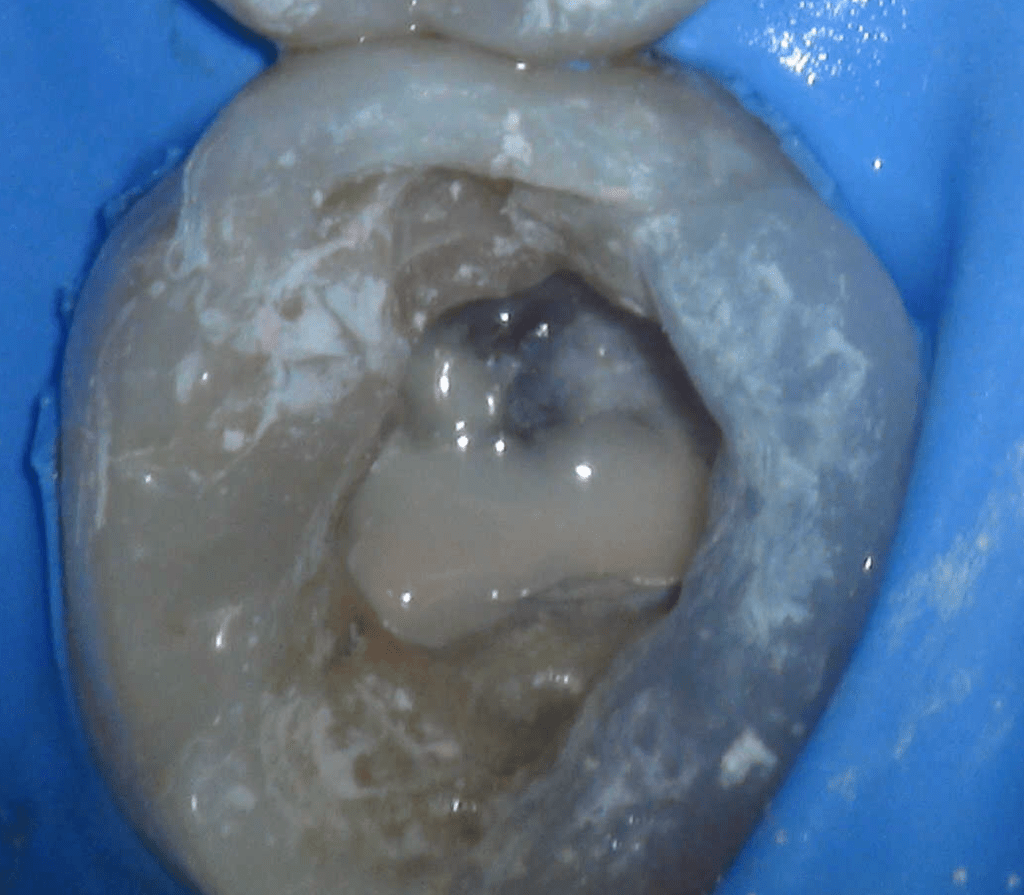

Reco preendo + 4 conductos molar superior